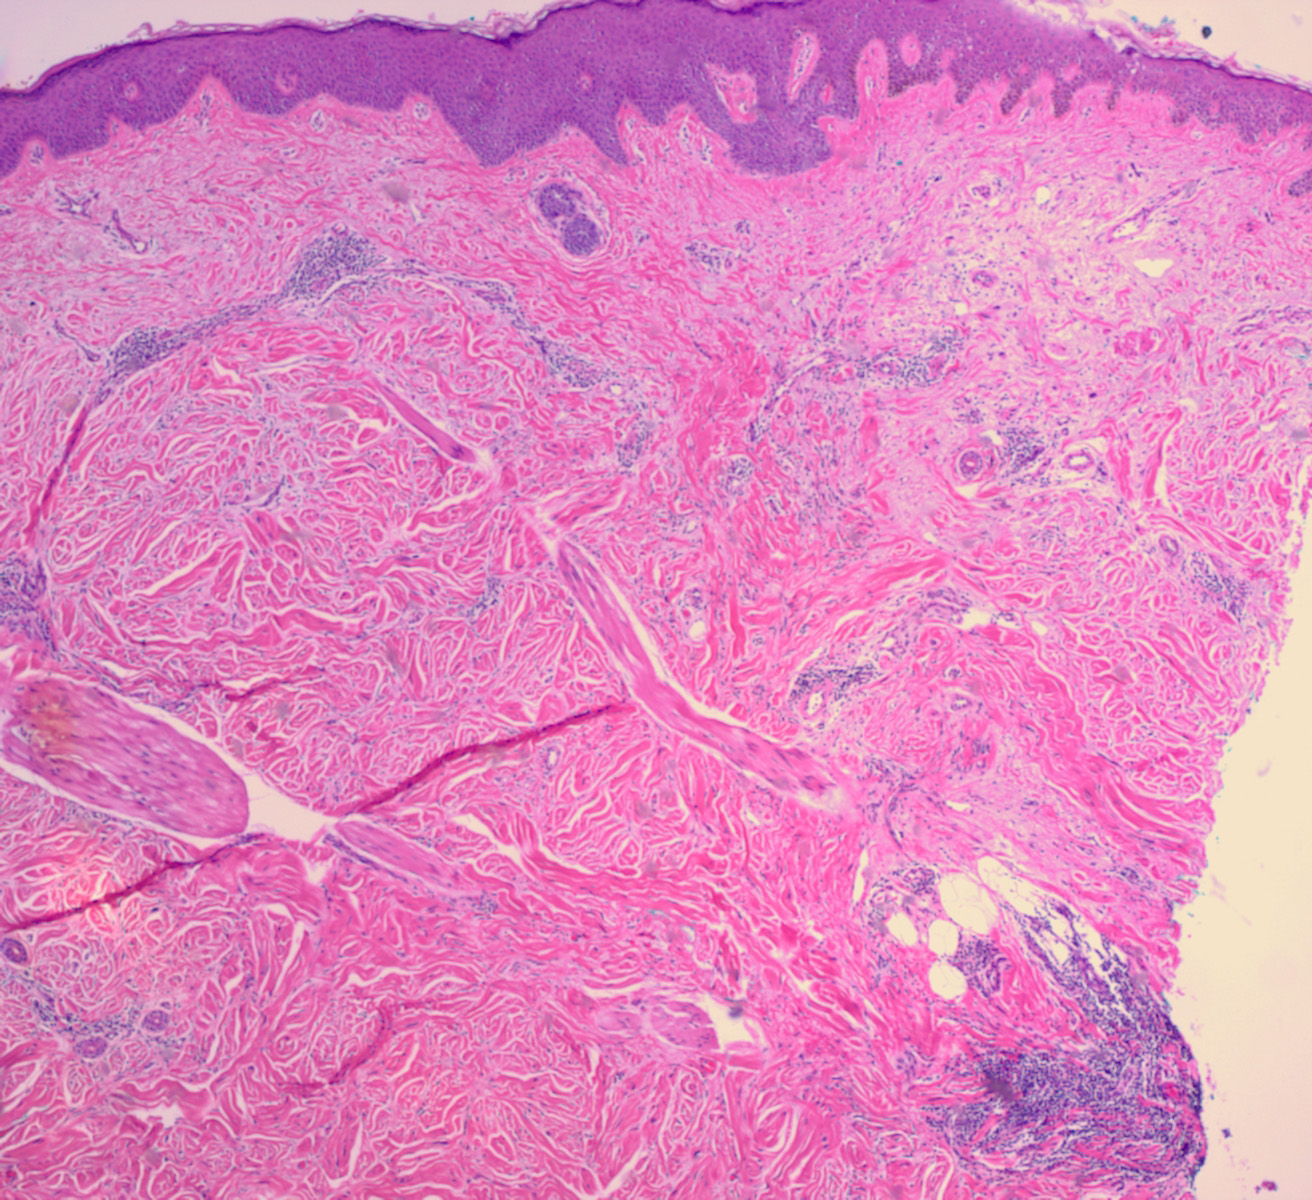

Desmoplastic melanoma = الميلانوم المكون للالتصاقات